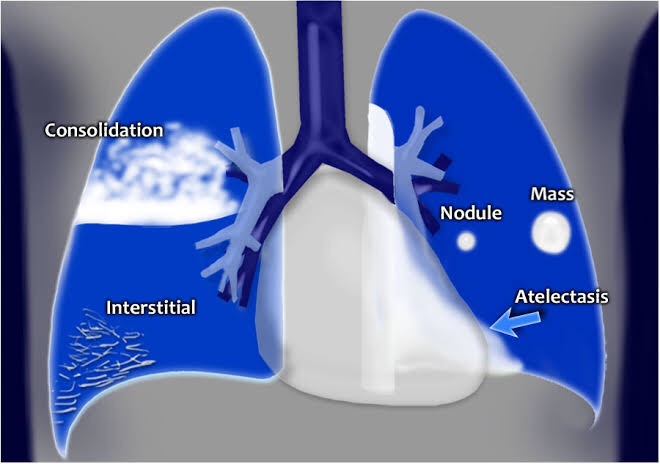

4) LUNG FIBROSIS & COLLAPSE

1) Homogenous opacities of one hemithorax

2) Elevation of dome of diaphragm

3) Shift of the Mediastinum to the affected side

▪️Causes:

▪️ Presentation:

- dependent on the underlying cause

- acute presentations will likely result in breathlessness

- more chronic collapse may remain asymptomatic

- symptoms may relate to the underlying cause, e.g. weight loss and cough

▪️Treatment:

- dependent on the cause of the collapse: foreign body should be removed

- mucus may respond to chest physiotherapy